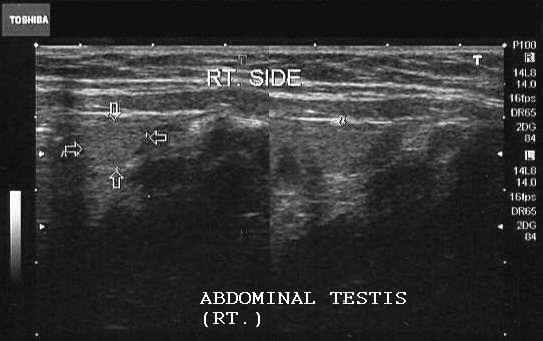

Ultrasound images of abdominal testis

Case-1

Sonography of the scrotum showed the left testis in its normal position within the scrotum. The right testis was not visualized within the scrotum but located just above the right inguinal canal (abdominal testis) (arrows).